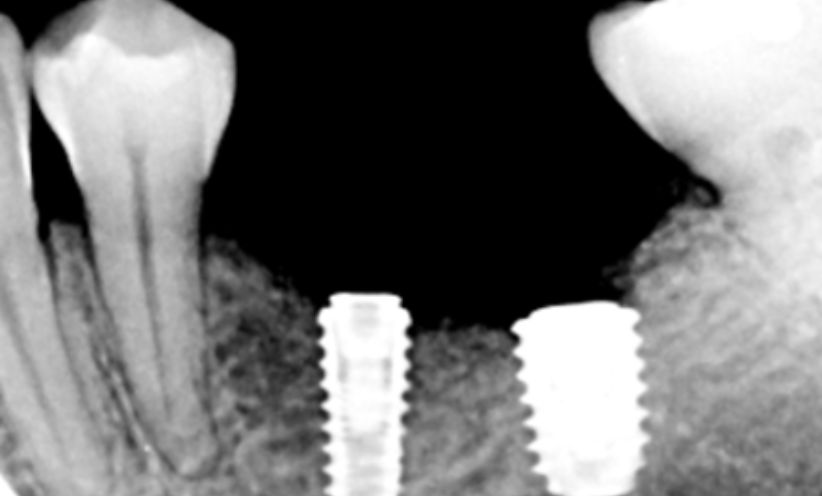

Before Xray - Abacus Dental

After Xray -Abacus Dental